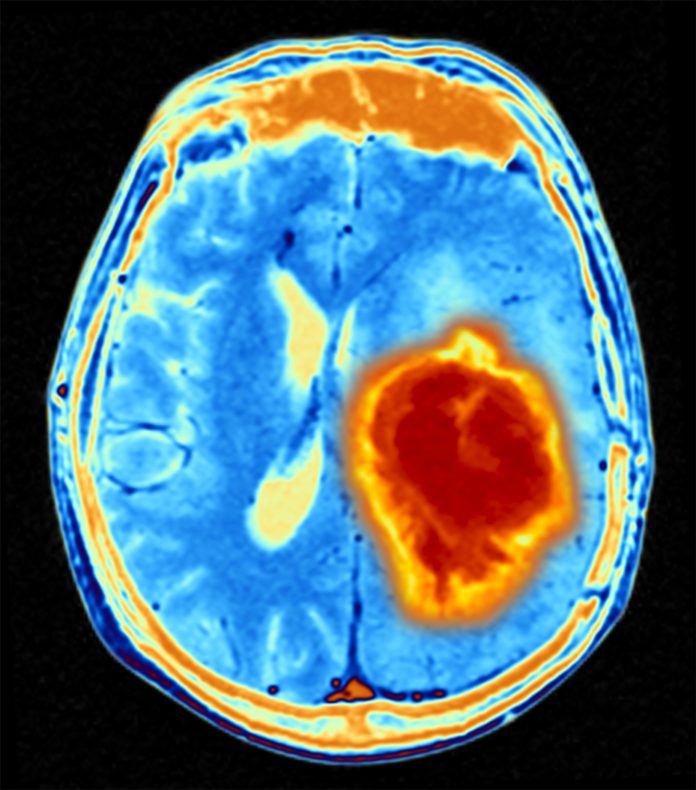

BrainIAC a fost mai eficient și în predicția subtipurilor mutaționale ale tumorilor cerebrale, oferind informații mai precise care ar putea ajuta la gestionarea clinică a acestora acolo unde biopsia țesutului nu este posibilă. Același lucru este valabil și pentru segmentarea gliomului, care poate ajuta la evaluarea sarcinii tumorale, planificarea tratamentului și monitorizarea bolii.

De asemenea, a avut o acuratețe superioară în predicția supraviețuirii după diagnosticul cu cancer glioblastom multiform.